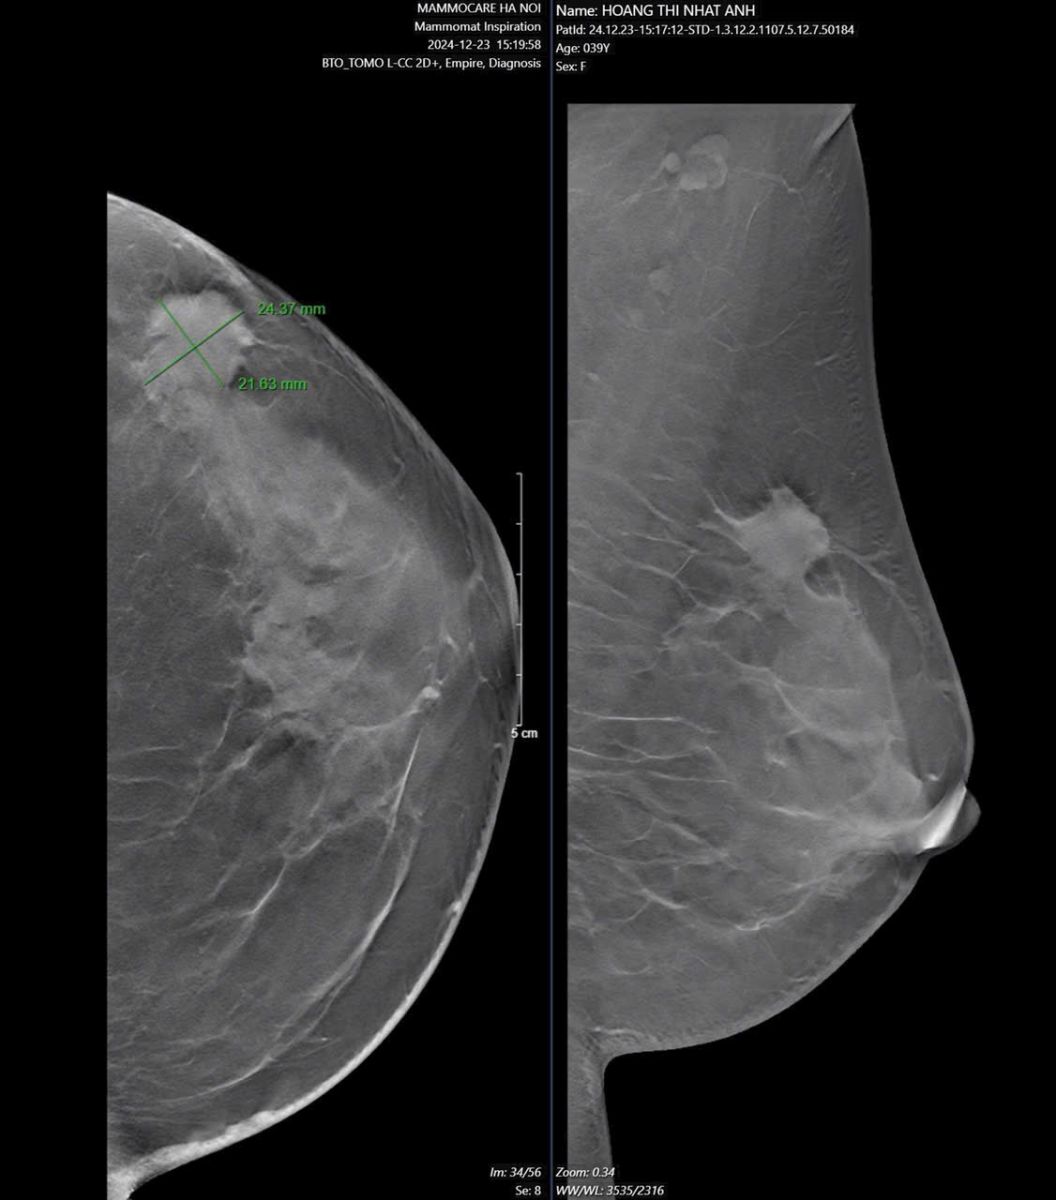

Một nữ bệnh nhân 39 tuổi đã thực hiện siêu âm vú trong lần khám sức khỏe định kỳ cách đây 3 tháng. Kết quả hoàn toàn bình thường, không có dấu hiệu đáng lo ngại. Tuy nhiên, khoảng một tuần trước, khi tự kiểm tra vú, cô phát hiện một khối u bất thường. Khi đi khám lại tại Trung tâm vú Mammocare, kết quả chẩn đoán xác nhận cô mắc ung thư vú.

Trường hợp này cho thấy rằng khám sức khỏe thông thường không phải lúc nào cũng đủ để phát hiện sớm ung thư vú. Dù siêu âm vú có thể giúp kiểm tra tình trạng tuyến vú, nhưng tầm soát ung thư vú chuyên sâu với các phương pháp hiện đại vẫn cần thiết để phát hiện bệnh ở giai đoạn sớm.